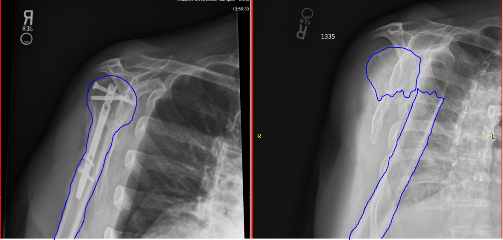

This implies that the broken pieces remain near their anatomic position and treatment merely requires immobilization in a sling until occasionally the rotator cuff muscles are injured or torn at the same time as the fracture.

However, the pain usually disappears before the fracture is stable healing times are different for every fracture and break. However, the pain usually disappears before the fracture is stable healing times are different for every fracture and break. Healing a broken bone takes time, and depends on several factors including patient age, overall health, nutrition, blood flow to the bone, and treatment. Sometimes, the surgeon will put in an artificial shoulder.